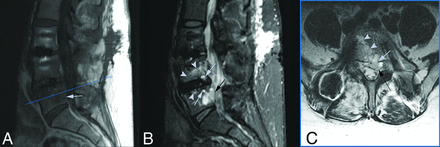

Images in a 56-year-old woman approximately 5 months following BMP–augmented extreme lateral and transforaminal lumbar interbody fusion of L3–L5 with persistent left-sided L5 radiculopathy. A, Sagittal T1-weighted MR image of the lumbar spine demonstrates a hypointense epidural collection at L5 (arrow). B, Corresponding sagittal STIR MR image shows the epidural cyst at L5 (black arrow), cystic osteolysis of the L4 and L5 vertebral bodies (white arrows), with endplate edema signal (arrowheads) and postoperative changes. C, Axial T2-weighted image at L5 (blue dashed line, A) illustrates the cyst (dashed black arrow) with the fluid-fluid level that narrows the left subarticular recess. Note the connection of the cyst to the bone resorptions within the vertebral body (arrowheads) and the discontinuity of the posterior longitudinal ligament (white arrow).

All patients demonstrated expansile cystic lesions within the lumbar epidural region located between the thecal sac and the intervertebral rhBMP-2-augmented graft. The epidural lesions had a characteristic MR imaging appearance with well-defined, occasionally lobulated T2-weighted hyperintense cysts. In 9 patients (56%), the cysts demonstrated internal T2-weighted hypointense fluid-fluid levels that gravitated and settled dependently, while MR imaging was acquired with the patient in a supine position. For all patients, a communication of the epidural collections with vertebral body resorptions adjacent to the graft was identified (Fig 1). The cysts were solitary in 1-level spinal instrumentations and limited to the level of the rhBMP-2 graft; however, in 3 patients (19%) with multilevel instrumentation, the epidural cystic lesions were distributed across >1 spinal level. Mass effect on the thecal sac and neural elements was observed in 8 patients (50%). Depending on the size and location of the epidural cysts, mass effect was exerted on exiting roots within the neuroforamen, traversing roots within the subarticular recess, or the thecal sac within the spinal canal.